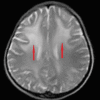

Figure 2. T2W image shows diffuse symmetrical, bilateral hyperintensities with a preponderance of frontal lobes (red arrows).

T2W image: T2-weighted image